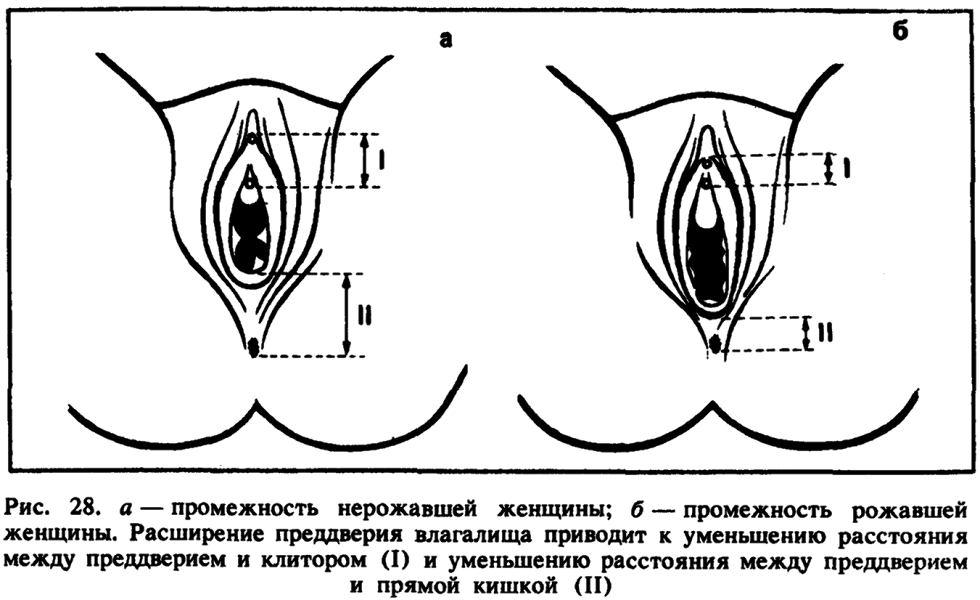

Anatomy of the female genital organs crotch

The structure of the female perineum

The difference that gave birth to and unbroken vagina